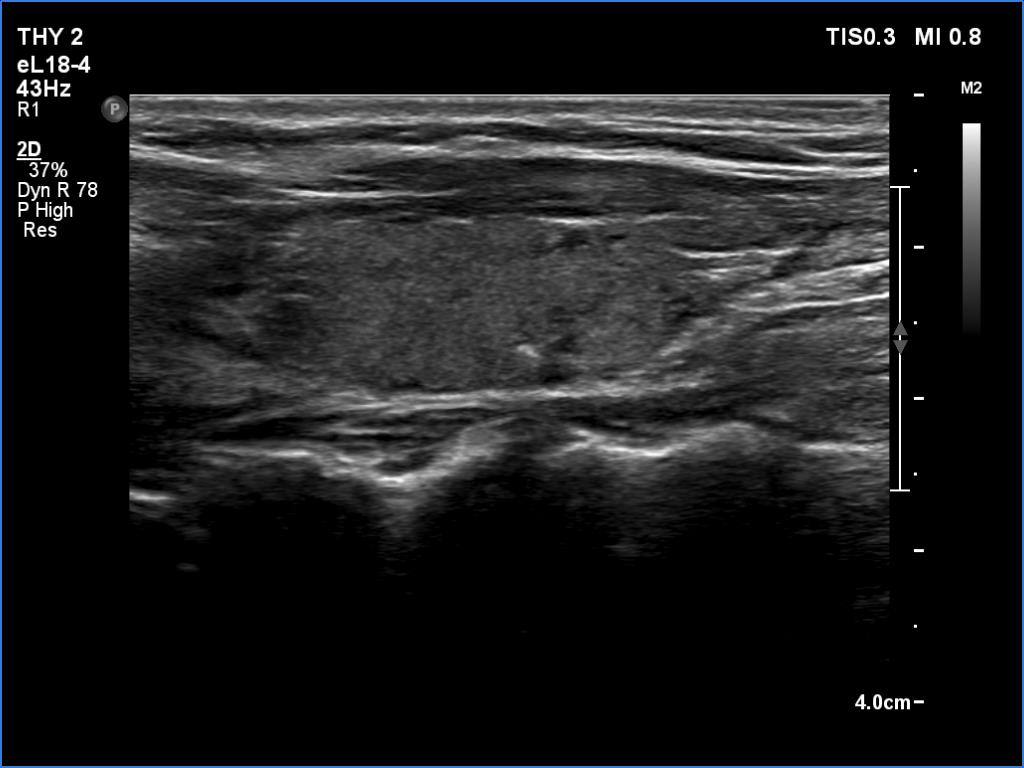

Ultrasonography. The thyroid was minimally hypoechoic and had several deeply hypoechoic discrete lesions. The latter had irregular margins and corresponded to more active foci of thyroiditis.